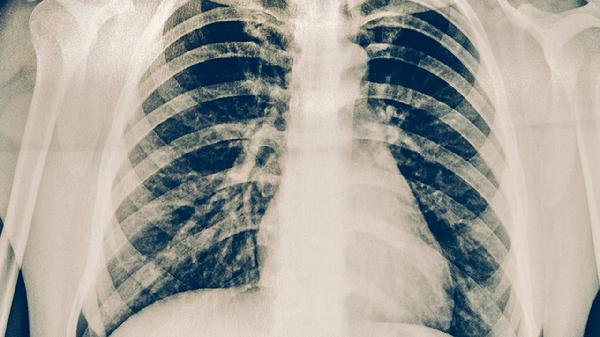

中医治疗慢性肺炎主要通过辨证施治结合中药调理、针灸疗法、拔罐疗法、饮食调养及运动康复等方式综合干预。慢性肺炎在中医属肺胀、肺痿等范畴,多与正气不足、痰瘀互结有关。

慢性肺炎患者需注意防寒避风,戒烟并减少油烟刺激。冬季佩戴口罩保护呼吸道,保持居室空气流通但避免直接吹风。定期复查肺部CT观察病灶变化,若出现咯血或持续高热应立即就医。中药治疗期间记录咳嗽频率、痰液性状变化以供医师调整方案。